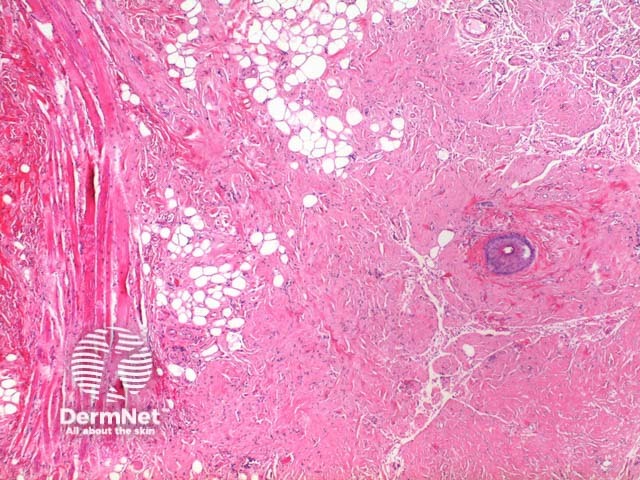

The scanning power view reveals a tumoral deposit within the dermis (figure 6). This may extend into the subcutaneous tissue (figures 7, 8, 9). Prominent clefting can be seen making superficial cases difficult to differentiate from colloid milium and paracolloid. The presence of numerous plasma cells in the accompanying inflammatory infiltrate, commonly with scattered Russell bodies, is helpful (figure 10).